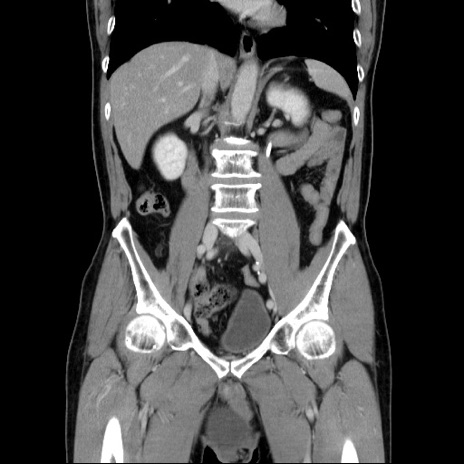

症例34(冠状断像)

【症例】60歳代 男性

【主訴】右鼠径部膨隆

【現病歴】1年程前より右鼠径部膨隆あり。自己にて還納可能だったため放置していた。3時間前より右鼠径部の脱出を認め、還納困難となり受診。

【既往歴】高血圧

【身体所見】右鼠径部に小児頭大の膨隆あり。弾性硬であり、用手還納は困難。左鼠径部にも膨隆を認める。脱出はなし。